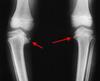

obese 3 y/o w/ unilateral bowing (30 deg) seen in image, what's the appropriate managment?

**infantile tibia vara (Blount's disease). ** The radiograph shows severe deformity with the characteristic Langenskiold stage 3 changes of the medial proximal tibial metaphysis that distinguish it from physiologic bowing. * **proximal tibiofibular osteotomy with acute correction into slight valgus** to unload the damaged area of the physis. This method provides the best results in patients younger than age 4 years. * Continued observation would result in progressive deformity. Bracing is most effective in younger children with less severe deformity. Lateral proximal tibial hemiepiphysiodesis relies on growth of the injured medial physis for correction and would result in severe tibial shortening in this young child. Complete epiphysiodesis also produces severe shortening and requires multiple lengthening procedures